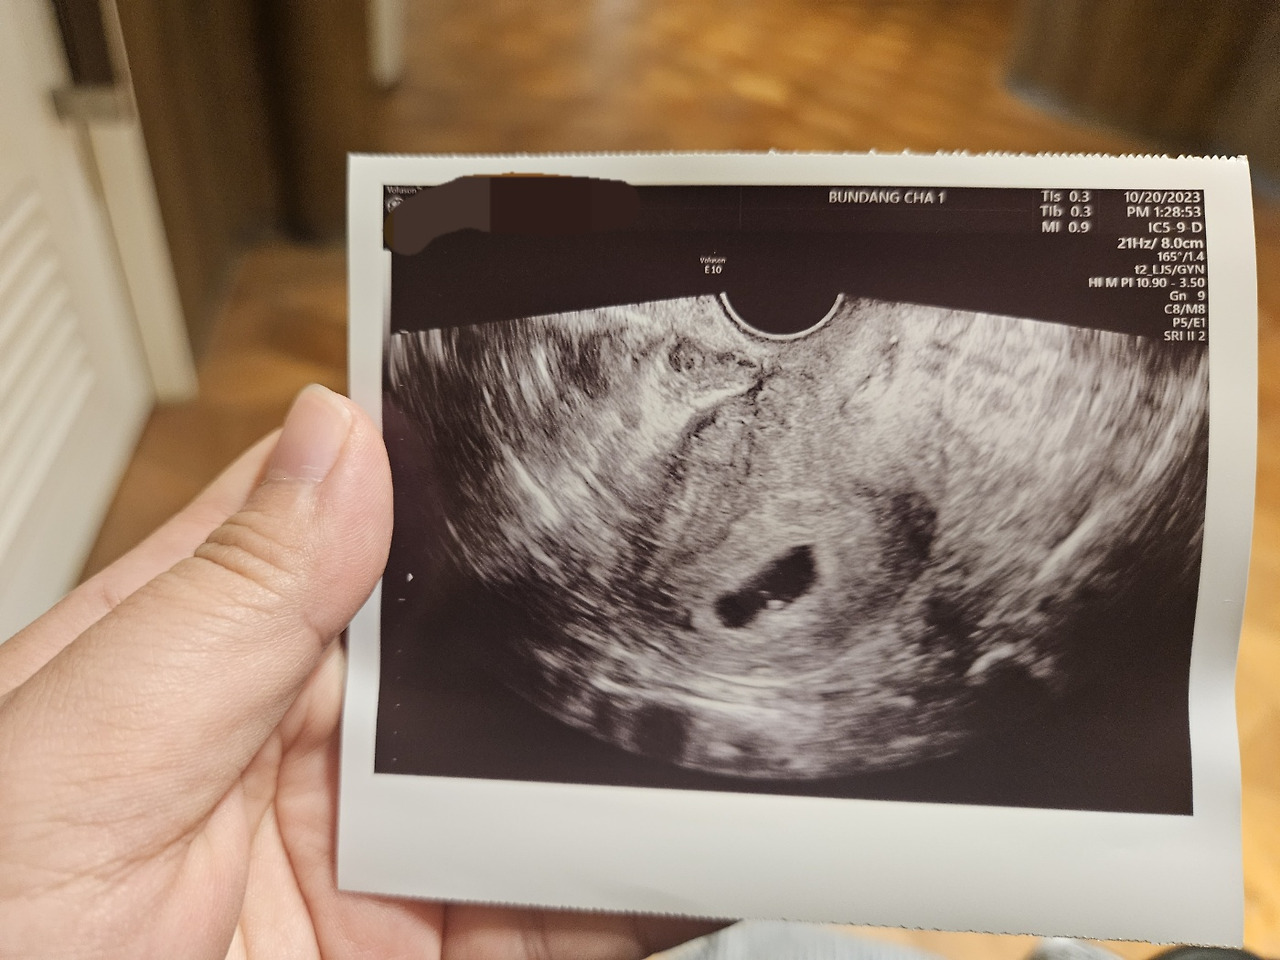

그리고 10일 뒤, 산전초음파를 보러 갔다.

화학적 증거를 확인했으니, 이번에는 병리학적 증거를 살펴볼 차례다.

KakaoTalk_20231020_142426037.jpg

자궁(포궁) 깊숙히 자리잡은 땅콩 모양의 아기집과 작은 심장이 뾸뾸거리는 작은 태아를 보았다.

크기는 0.2~3mm 정도로 아주 작은 상태다.

살아보겠다고 그 작은 심장이 명멸하는 것이 무척이나 대단해보였다. 이게 생명의 신비인가.

화학적 증거, 병리학적 증거 모두 임신이라고 말하고 있었다.

소중한 아기가 복중에 자리잡았다.